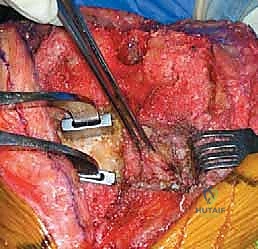

الركبة المتصلبة تكون قاسية جداً ويصعب كشفها بالطرق العادية. يستخدم الدكتور هطيف تقنيات جراحية دقيقة لحماية الوتر الرضفي من التمزق، وقد يتطلب الأمر إجراء قص عظمي بسيط في نتوء الساق (Tibial Tubercle Osteotomy) أو قص في وتر العضلة الرباعية (Quad Snip) للوصول الآمن للمفصل.

الخطوة الثالثة: الاستئصال الجذري للأنسجة الندبية (Radical Synovectomy)

يتم إزالة كافة الأنسجة المتليفة والندبية الكثيفة (Scar tissue) التي تكونت في الجيوب المفصلية وخلف الركبة. هذه الخطوة وحدها كفيلة بتحرير جزء كبير من حركة المفصل.

الخطوة الرابعة: إزالة المكونات القديمة بدقة

بأدوات متخصصة، يتم استخراج المكونات المعدنية والأسمنت العظمي القديم بحذر شديد للحفاظ على أكبر قدر ممكن من العظام السليمة للمريض.